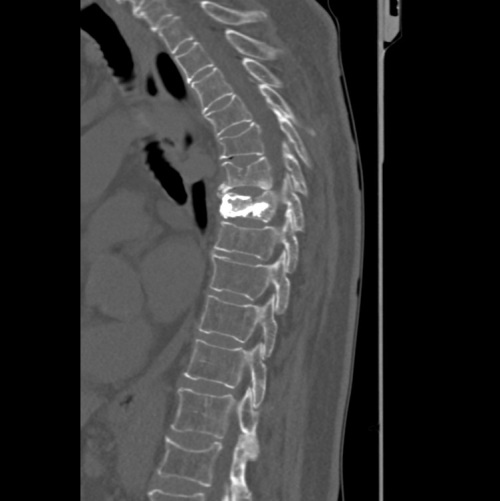

Beispiel Verletzung der Wirbelsäule

Wenn es sich nicht nur um eine Zerrung oder Verstauchung handelt, sondern um einen Bruch von Wirbelkörpern, dann muss meistens schnell gehandelt werden. Neben den gängigen Standardoperationsverfahren mit Titanimplantaten zum Wirbelkörperersatz können wir in unserem Haus auch minimalinvasive Operationen anbieten.